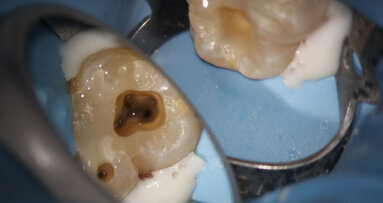

For CAD/CAM applications, either the highly esthetic IPS e.max CAD ceramic glass blocks or the high-strength IPS e.max ZirCAD zirconium oxide can be selected, depending on the case requirements (Fig. 1).

Based on its physical and esthetic properties, e-max was chosen as the restorative material. Wax patterns were developed for pressing, simulating a “cut back” upon which final porcelain layering could be accomplished.